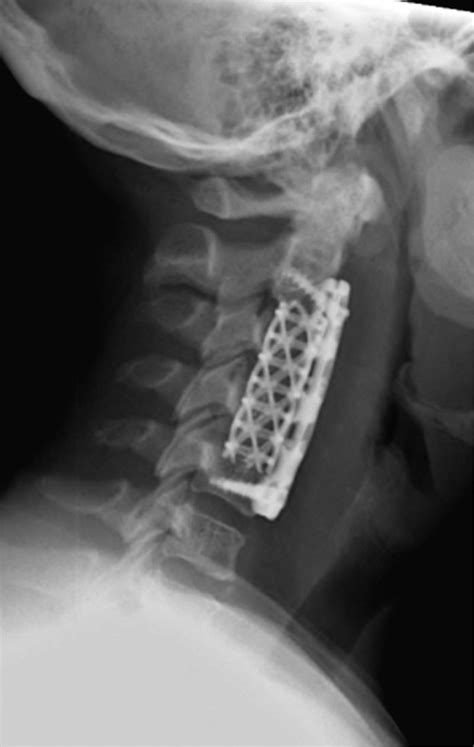

• Fusion: The disc space is replaced with a bone graft or synthetic implant, sometimes held in place with a small titanium plate and screws for added stability.